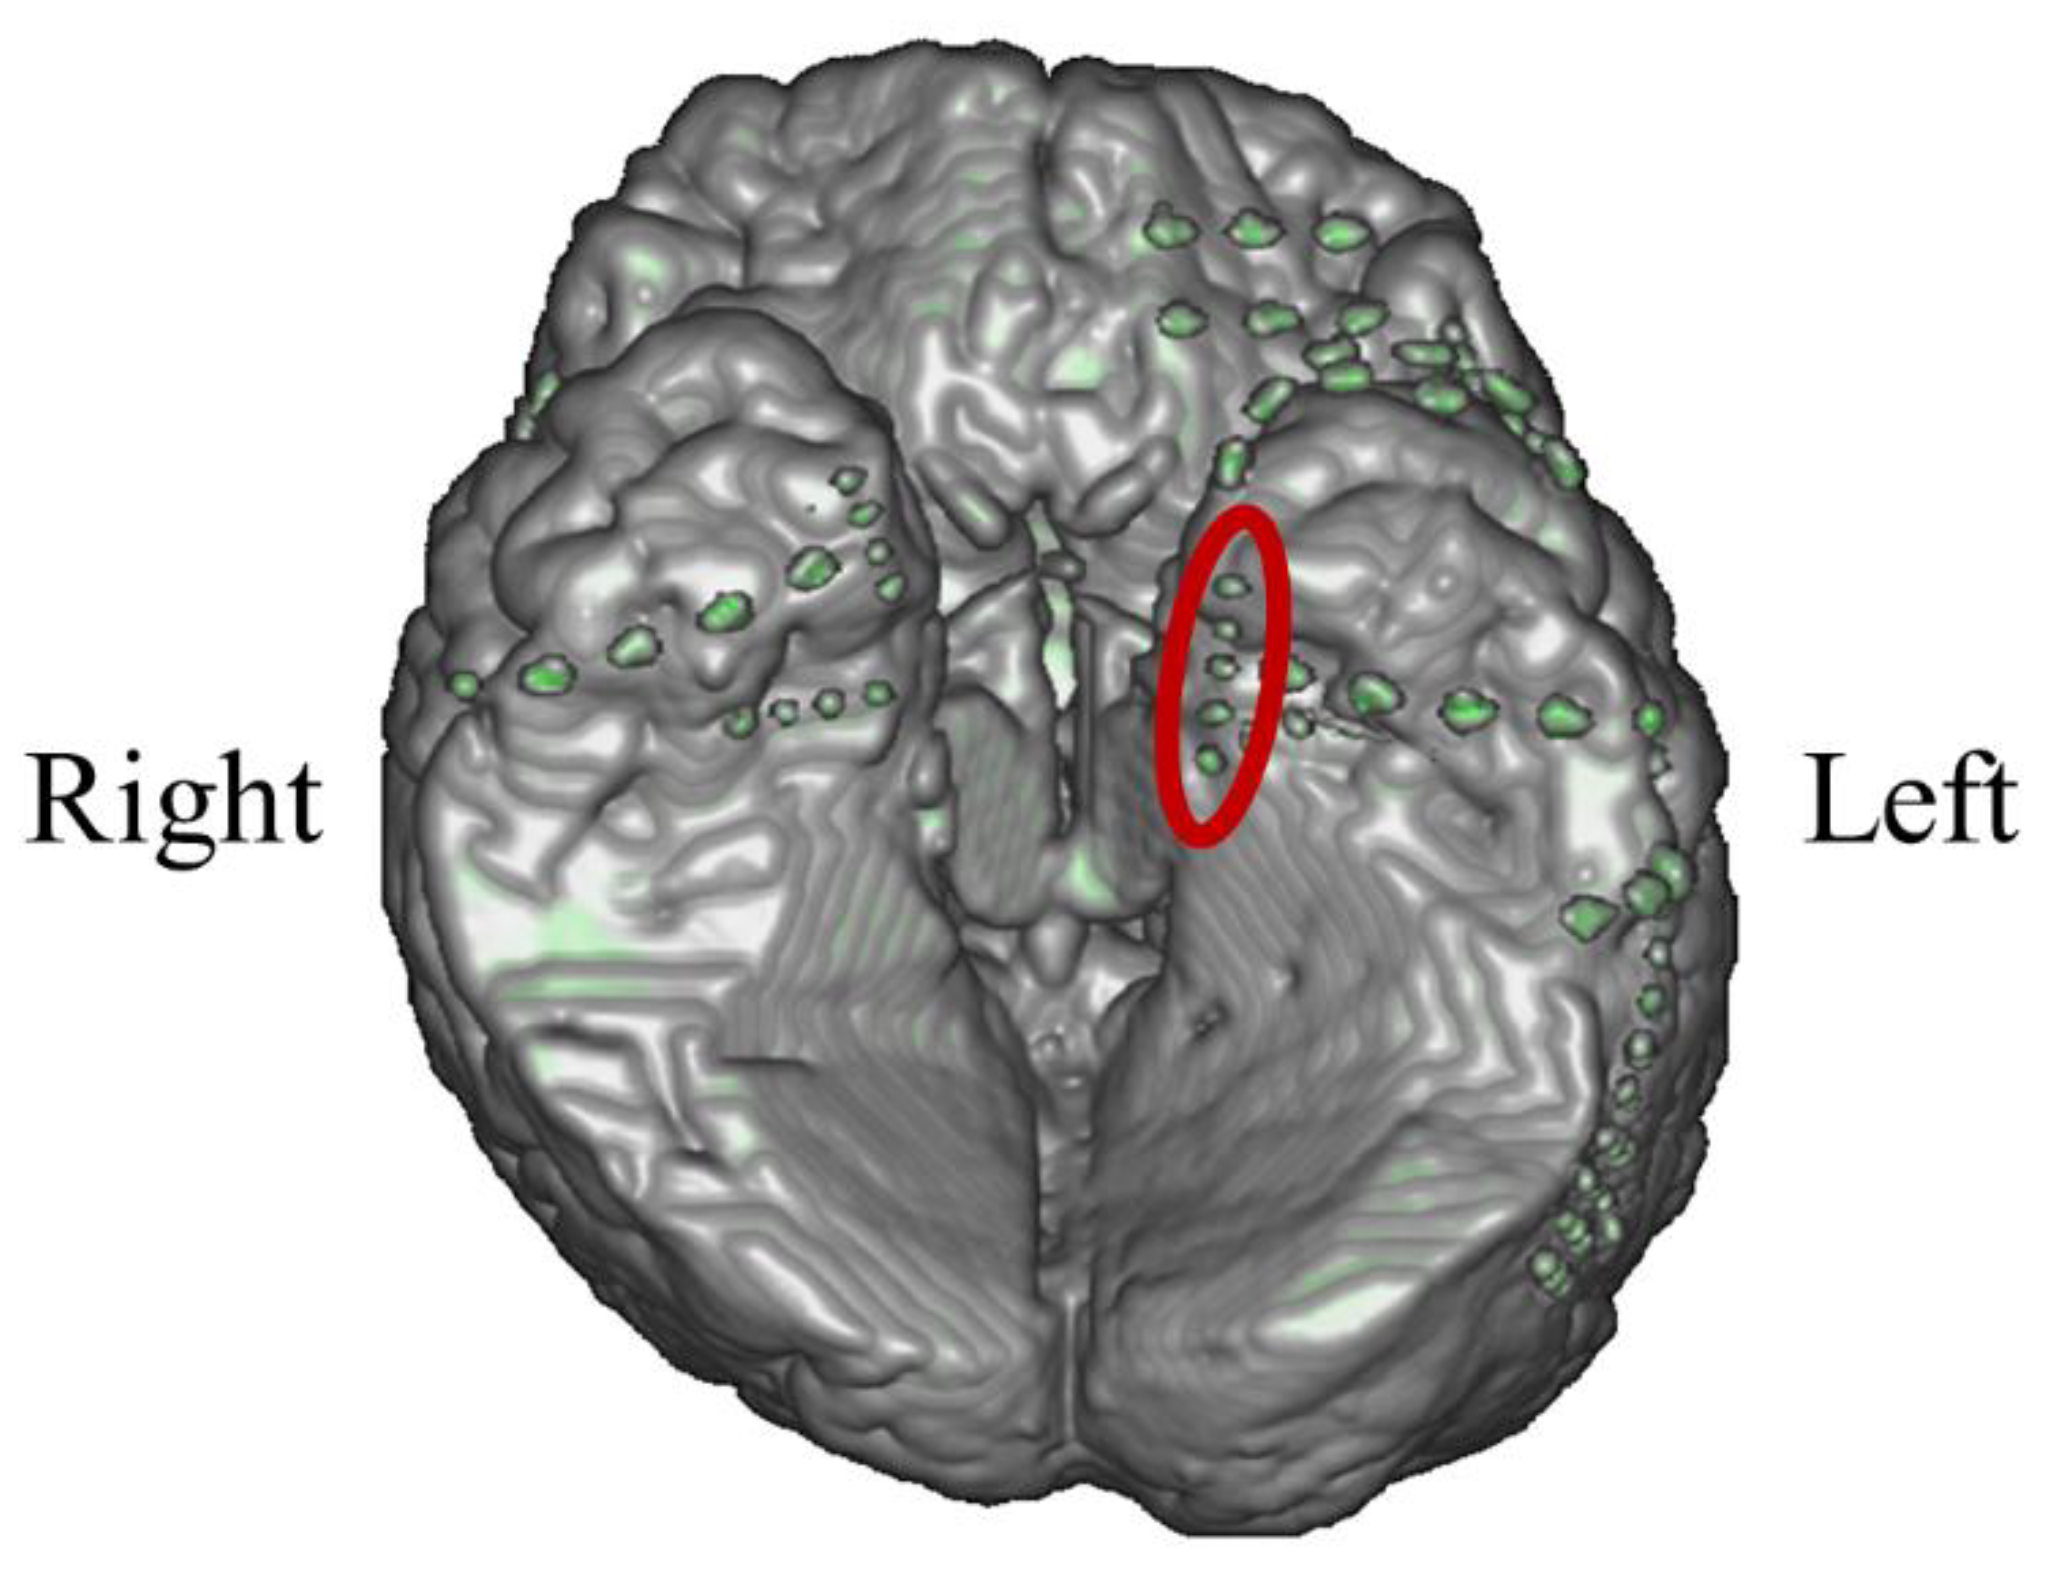

3.2.1. Intracranial Electrodes Used for Memory NF (P02)

3.3.1. Intracranial Electrodes Used for Memory NF (P03)